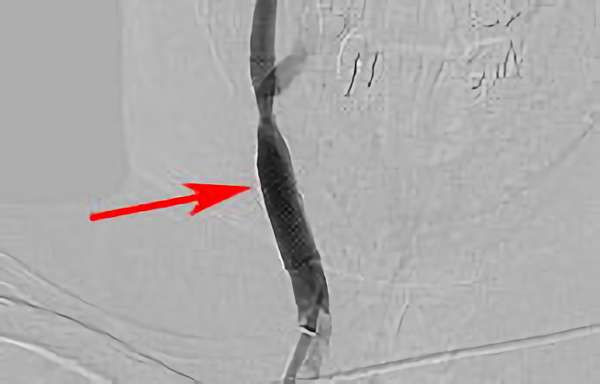

200

'18年7月31日

内頚動脈狭窄症

80代

大阪府の病院